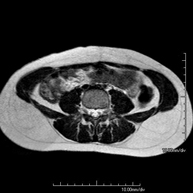

Prueba diagnóstica no invasiva que consiste en la obtención de imágenes de alta definición anatómica de la glándula prostática mediante el empleo de un campo electromagnético y ondas de radio (con un emisor y un receptor). No utiliza radiación ionizante. Se utiliza una bobina endorrectal para obtener imágenes de máxima definición anatómica de la próstata, que permitirá realizar el estudio espectroscópico (estudio a nivel molecular que ayuda a diferenciar las células de origen maligno o tumoral). También se realiza el estudio con contraste paramagnético que aporta una mejor definición tisular. Esta prueba dura unos 40 minutos, durante los cuales el paciente deberá estar lo más quieto posible. Como preparación previa requiere limpieza del colon. Esta prueba está especialmente indicada en aquellos pacientes con sospecha de neoplasia de próstata, con neoplasia de próstata conocida para el estadiaje tumoral, estudio de localización del tumor prostático como guía o mapa para la biopsia, seguimiento de los pacientes con neoplasia de próstata tratados con tratamiento quirúrgico o radioterápico, sospecha de recidiva de la neoplasia de próstata, etc. - RM Cuerpo entero (Total body)